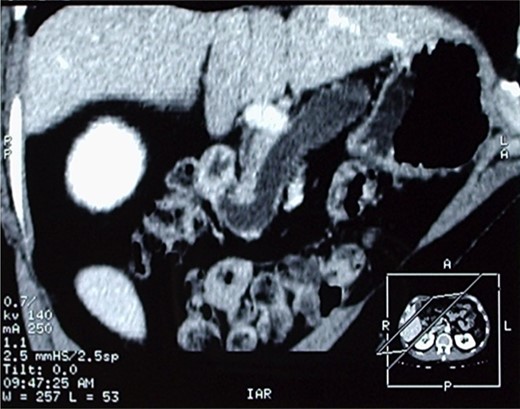

The patient therefore underwent a computed tomography (CT) scan (Figs 1 and 2) that revealed ‘a thickened duodenal wall and a sero-cystic lesion of the pancreatic head without contrast-enhancement, which compressed the duodenal lumen and caused a dilation of the Wirsung duct’. The liver, the gallbladder and the extrahepatic biliary tree were normal. No lymphadenopathy was found.

Another image of the CT scan, showing a sero-cystic lesion of the pancreatic head.